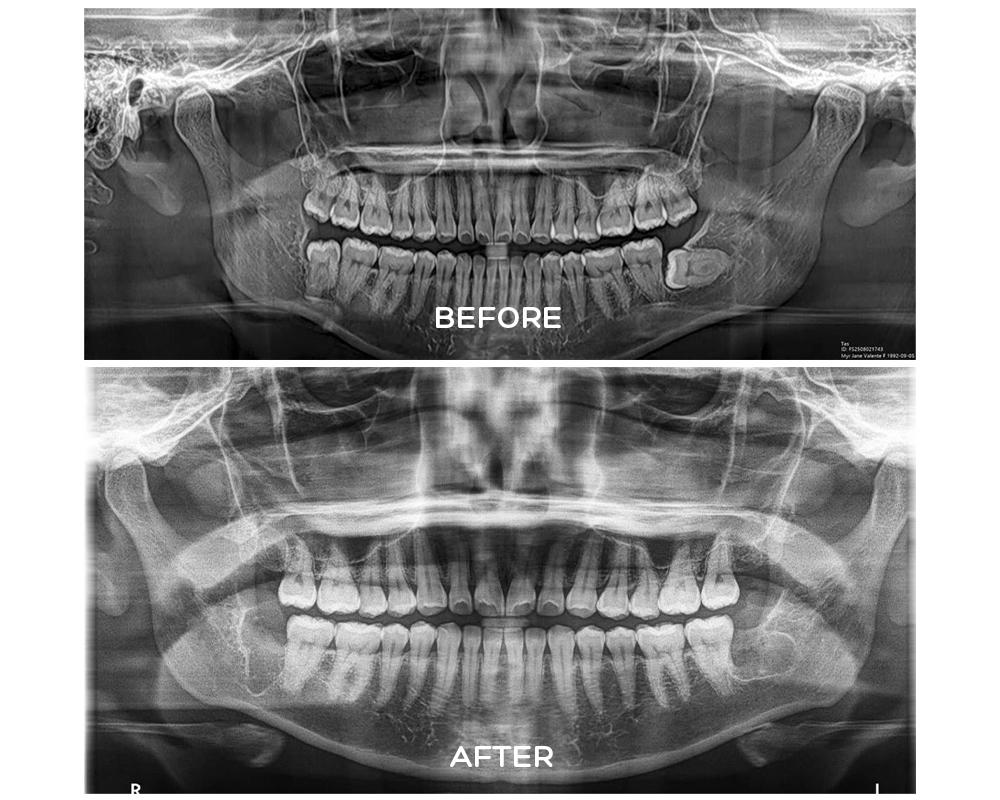

Wisdom teeth are the last set of molars to develop. Because modern jaws are often smaller than those of our ancestors, there may not be enough space for them to grow properly. This can lead to impaction, where the tooth becomes trapped beneath the gums or bone. Impacted teeth may cause swelling, jaw stiffness, bad breath, and even damage to nearby teeth. Dentists typically recommend removal when these complications arise or when X-rays show a high risk of future problems.

A wisdom tooth extraction may be simple or surgical, depending on the tooth’s position. A simple extraction is performed when the tooth has fully erupted and can be removed with forceps. Surgical extraction is required if the tooth is impacted or partially erupted. In this case, the dentist or oral surgeon may need to make a small incision in the gum or remove some surrounding bone.